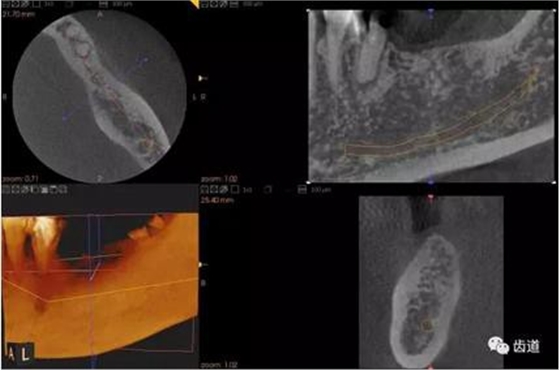

二)牙槽骨外科

CBCT在牙槽骨外科手術(shù)中,通過立體影像可以全面了解牙齒周圍的解剖結(jié)構(gòu),牙根的位置,下頜神經(jīng)管的走向和范圍,上頜竇底的位置及上下牙牙根與上頜竇的關(guān)系,下牙牙根與下頜神經(jīng)管的位置關(guān)系,手術(shù)時(shí)就會“有的放失”,采用更加安全的方法,避免損傷上頜竇和下牙槽神經(jīng)。

2、下頜磨牙阻生

下頜第二第三磨牙阻生口腔曲面斷層片影像

下頜第二第三磨牙阻生CBCT影像定位

三種圖片的影像學(xué)比較